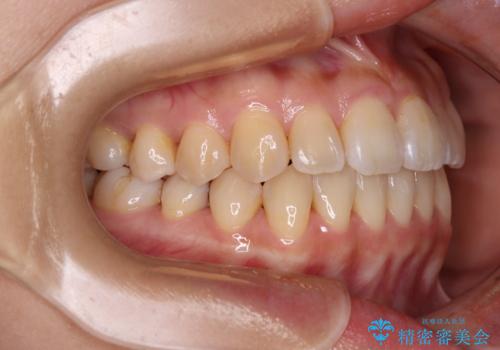

- 前歯のクロスバイトを改善したいとのことで来院された患者様です。

舌の突出癖が認められたため、デコボコ改善に伴い前歯が前突する可能性があったため、舌のトレーニングをしっかりと行うよう指導しながら治療を進めることとしました。

左下の奥歯は根管治療後に放置されていたため、咬み合わせを調整しながら矯正治療を行い、最後にオールセラミッククラウンにて補綴治療を行うこととしました。